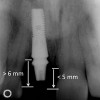

Figure 4  Characterization of the interproximal bone and tooth contacts: A periapical radiograph assists in measuring the distance from bone crest to the adjacent tooth contact points for missing tooth No. 8. The mesial bone crest to the adjacent tooth contact distance is < 5 mm, while the distal bone crest to adjacent tooth contact distance is > 6 mm (Fig 4). One-year following implant placement, conservation of these dimensions is revealed (Fig 5). The clinical photograph (Fig 6) of the lateral incisor adjacent to tooth No. 8 implant crown demonstrates that the absence of distal interproximal (papilla) fill related to the observed bone crest to contact distance exceeds 6 mm.

Figure 4

Figure 5  Characterization of the interproximal bone and tooth contacts: A periapical radiograph assists in measuring the distance from bone crest to the adjacent tooth contact points for missing tooth No. 8. The mesial bone crest to the adjacent tooth contact distance is < 5 mm, while the distal bone crest to adjacent tooth contact distance is > 6 mm (Fig 4). One-year following implant placement, conservation of these dimensions is revealed (Fig 5). The clinical photograph (Fig 6) of the lateral incisor adjacent to tooth No. 8 implant crown demonstrates that the absence of distal interproximal (papilla) fill related to the observed bone crest to contact distance exceeds 6 mm.

Figure 5

Figure 6  Characterization of the interproximal bone and tooth contacts: A periapical radiograph assists in measuring the distance from bone crest to the adjacent tooth contact points for missing tooth No. 8. The mesial bone crest to the adjacent tooth contact distance is < 5 mm, while the distal bone crest to adjacent tooth contact distance is > 6 mm (Fig 4). One-year following implant placement, conservation of these dimensions is revealed (Fig 5). The clinical photograph (Fig 6) of the lateral incisor adjacent to tooth No. 8 implant crown demonstrates that the absence of distal interproximal (papilla) fill related to the observed bone crest to contact distance exceeds 6 mm.

Figure 6